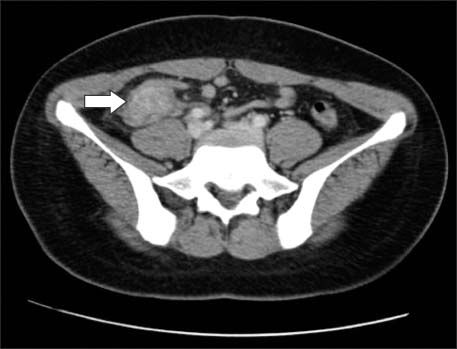

A contrast-enhanced abdominal CT scan revealed a 4.3×2.3 cm mass-like lesion beneath the cecum in the RLQ and an invisible normal appendix (Fig. 1).

Fig. 1

CT image shows a 4.3×2.3 cm mass-like lesion beneath the cecum within the right lower quadrant (arrow). This finding suggested differential diagnosis of advanced appendicitis with phlegmon or a tumorous condition.

Fig. 1 CT image shows a 4.3×2.3 cm mass-like lesion beneath the cecum within the right lower quadrant (arrow). This finding suggested differential diagnosis of advanced appendicitis with phlegmon or a tumorous condition.